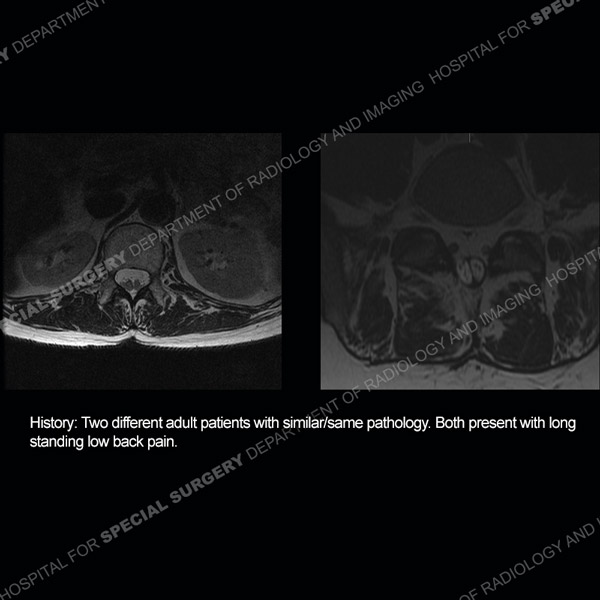

![]() |

Featured Case of the MonthCase 215: 85-year-old woman with recent exacerbation of left lateral hip pain.

|